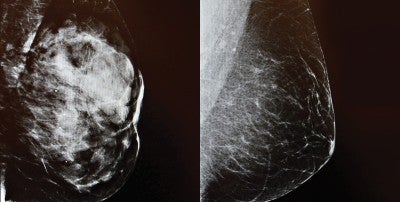

3D imaging Mammogram at LVHN

Mammography is an important tool to screen for breast cancer, but dense breast tissue can hide cancer from view. Dense breast tissue has a larger percentage of fibroglandular tissue relative to fat. It appears white on a mammogram, as do tumors, making it harder to detect abnormalities. However, mammography is still considered an important screening tool, even for women with dense breasts.